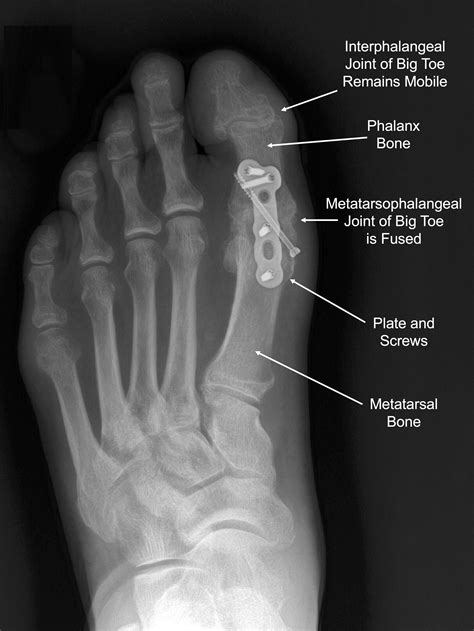

• Arthrodesis (Fusion): This is considered the "gold standard" for advanced cases. The two bones forming the MTP joint are fused together. While this eliminates motion in the joint, it also eliminates the pain, allowing for a normal walking gait.

• Arthroplasty: This involves replacing the joint surfaces with an implant. It is generally reserved for less active individuals or cases where preserving joint motion is critical.